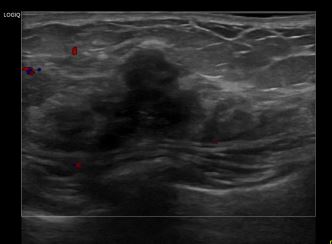

상기환자는 우측유방 만져지는 멍우리로 내원하신 50대 후반 여성분으로 의심스러운 우측혹 조직검사 시행해 유방암 진단되었습니다.